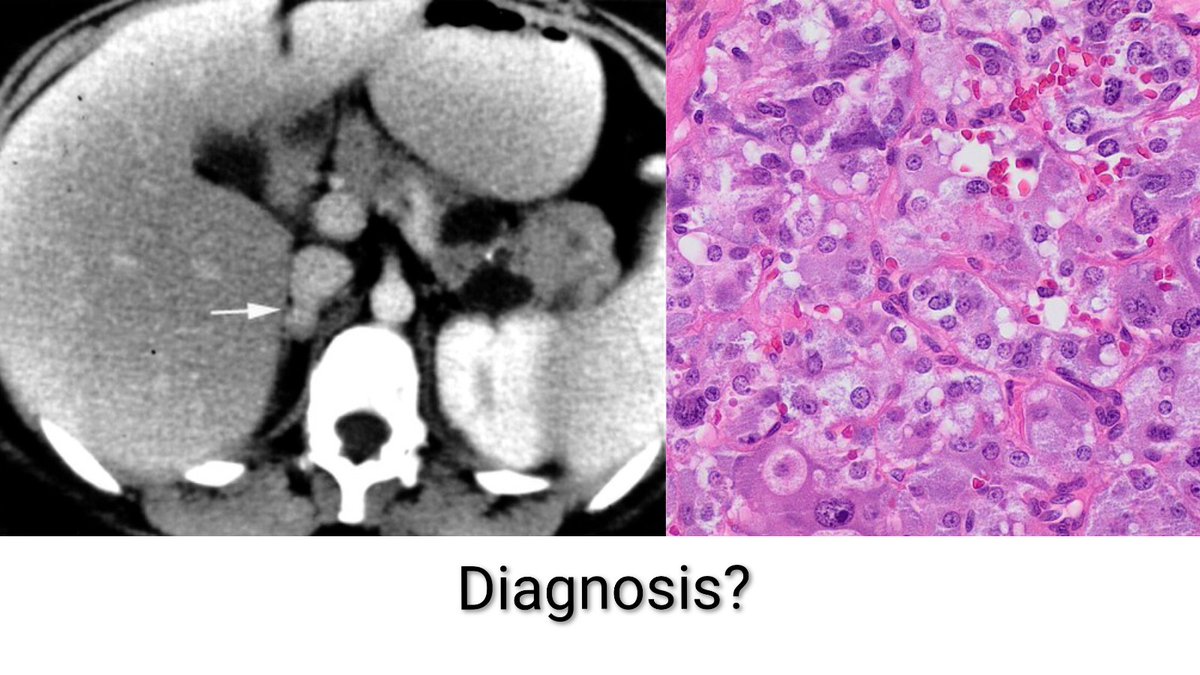

⭕ A 35 year old female presents with recurrent episodes of headache, palpitations & excessive sweating for the past 6 months. Her blood pressure during episodes is 200/110 mmHg. CT scan & Histopathology images are shared below. What is the diagnosis? A) Adrenocortical

⭕ A 35 year old female presents with recurrent episodes of headache, palpitations &amp; excessive sweating for the past 6 months. Her blood pressure during episodes is 200/110 mmHg. CT scan &amp; Histopathology images are shared below. What is the diagnosis?

A) Adrenocortical